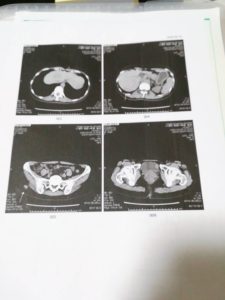

先日のMRI、CTの結果膀胱

膀胱の腫瘍のMRI、CTを見て何かわからんと。

あと、南医師からCT見たら肺に影があるから、腫瘍内科に行けと。

この影、6月にCT、MRI撮ったときもあるし、典型的なリンパ腫の病巣やから、